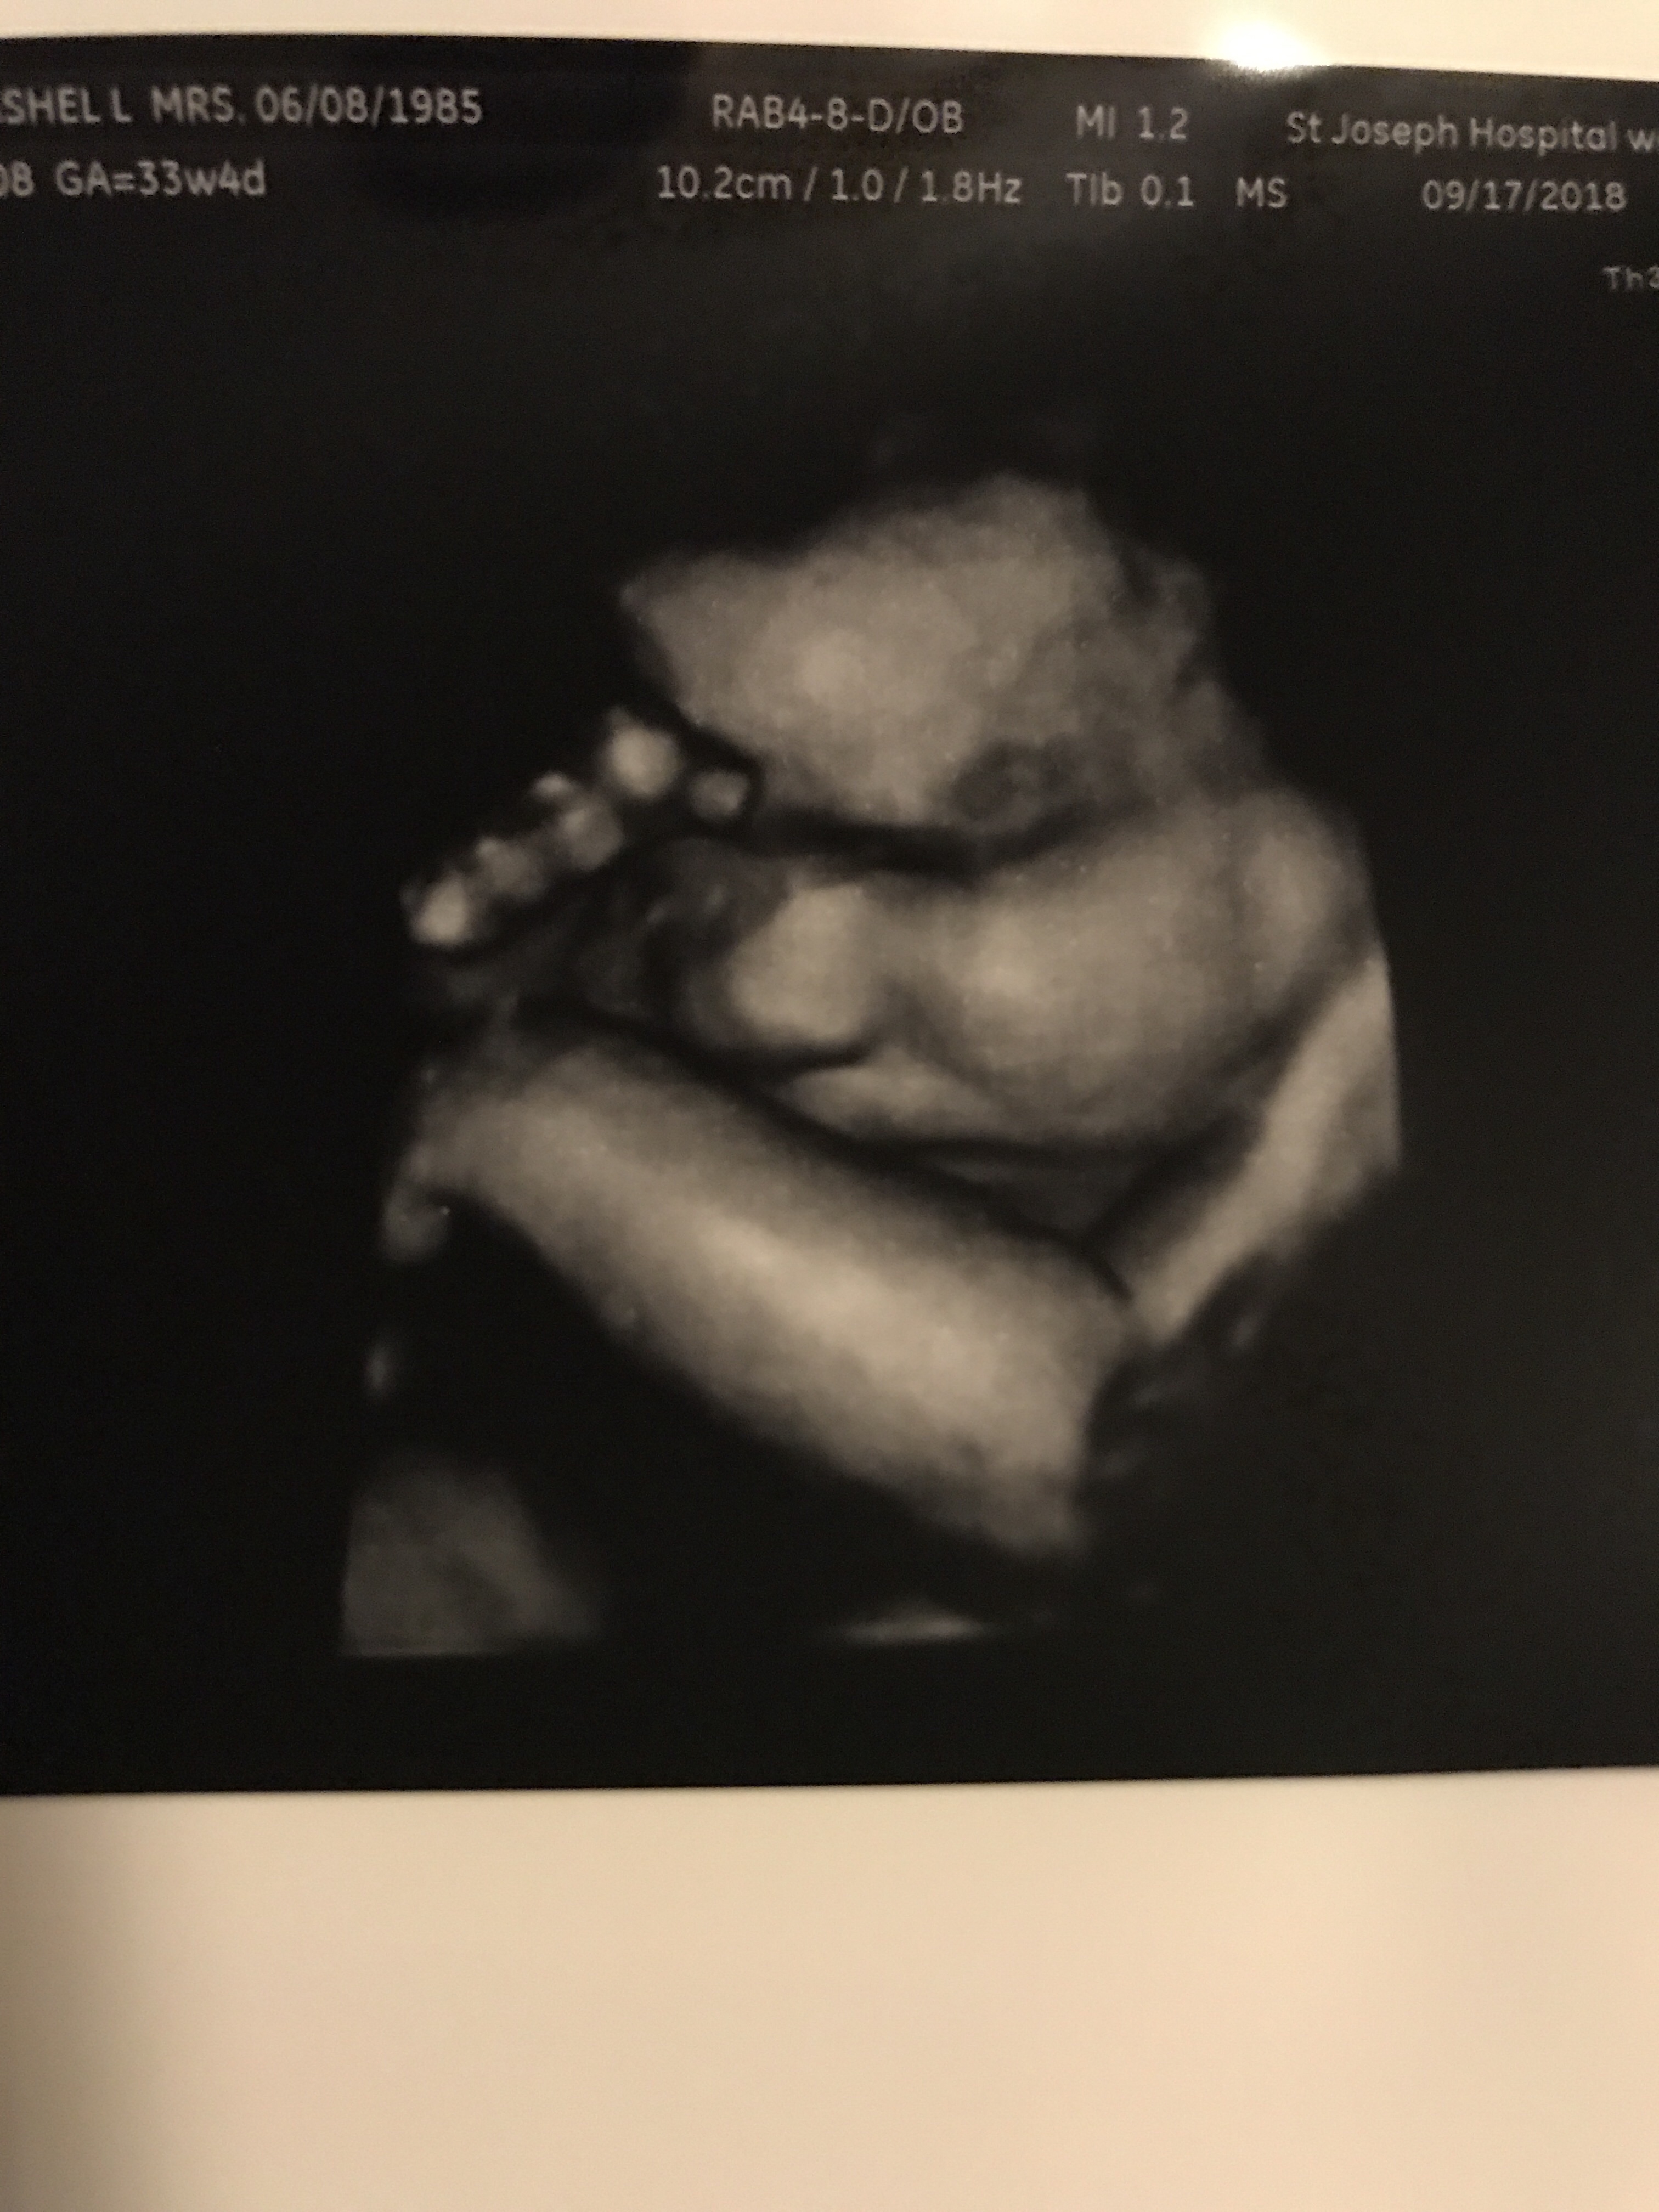

Things are going well. Baby B is enjoying life on the inside. He likes to kick and play often. We love our fun time together as long as it’s not in the middle of the night. Haha. I’m definitely getting more stretching ligaments if you have had them you know they are zero fun. If you haven’t let me try to explain. It’s basically like you move from any normal position and all the sudden it feels like someone has a huge sharp knife and they are stabbing you with it. Every time you try to move or adjust the knife is being twisted viciously. This happens always by surprise you never know when to expect the knife fight but let me tell you I always lose lol. I’m still eating all my ice! I love love LOVE crunching on ice. I’m definitely getting more round and I freaking love it! People can tell now so that’s great. I look super cute in clothes! Now out of clothes not so much… I have had a few Braxton-Hicks from time to time usually when I’m busy at work and not drinking enough water. I asked Dr. Google since it seemed a bit early and of course he said it’s normal when you have had a few pregnancy’s. I guess number 5 counts as a few! I also followed up with my real dr who also said yep it’s fine! I still feel super lucky I haven’t gained any weight yet and I feel great. Sometimes I get a bit winded and I can’t eat a ton but that’s all fine! Our next appointment I will be 28 weeks so it’s basically a all day appointment since I have to do my sugar test plus another ultrasound since baby B wasn’t very cooperative at the 20 week ultrasound. Then I’ll meet the dr and then get to go home. I’m not allowed to eat two hours before my test so when I leave I’m sure I’ll be starving! I wonder if it would be frowned upon if I ordered a pizza or something and delivered it to my dr office while I wait??? I sure hope my sugar test comes back good this time. Last time it was close so they made me do the long 3 hour test! Then we get to go see my Dr every two weeks! This pregnancy is flying by. I love and hate the end! I’m so happy and excited for J and K to get their sweet baby boy! Plus I’m so excited to give birth and see what he looks like! I just always feel a little sad that I won’t be pregnant anymore. I feel so incredibly blessed that his mommy and daddy picked me to help keep him safe until he is big enough to go home and live with them. I can’t begin to explain how humbling and special that is to me! Everyone loves to say what a incredible person I am, but really the incredible people are baby B’s parents! To put that kind of trust into anyone is incredible! I’m so happy out of all the people they could have picked they chose me. I also can’t help but be a bit jealous this sweet baby boy gets to go live by the ocean! What a lucky boy he is! Now let’s see what baby B is up to this week! Plus a few pics!